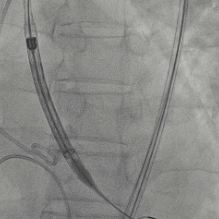

患者病史 主诉:发作性胸闷憋喘半年,加重伴呼吸困难2周。 现病史:患者半年前无明显诱因出现胸闷、憋喘,伴有下肢水肿,2周前上述症状明显加重,夜间不能平卧,痰中带血丝,为进一步诊治再次来我院,门诊以"心力衰竭"收入院。 既往史:肾功能不全、心房颤动 心脏超声提示:LVEF:0.54 1.主动脉瓣病变;2.主动脉瓣狭窄(重度)并反流(中度);3左室壁节段性运动不良;4.升主动脉扩张、双房扩大、左室肥厚;5.二尖瓣硬化并反流(中度);6.三尖瓣反流(轻-中度);7.肺动脉瓣反流;8.肺动脉高压(轻度)PGmean=105mmHg,Vmax=635cm/s,瓣口面积0.27cm²。 术前CT评估 Type0型二叶瓣,重度钙化,钙化集中在瓣叶游离缘,右冠窦为著;左冠高度11.8mm,由于左冠窦部空间较小,左冠风险较高, 升主动脉扩张,最宽处50.5mm;主动脉瓣环水平夹角61.5°,横位心。主动脉弓角77.6°,锐角弓,外周入路在腹主及髂总处有大量散状钙化,胸主处有81.6°的迂曲。 手术策略 推荐右侧股动脉为主入路,左侧股动脉为辅入路,送snare辅助过弯,使用18F大鞘,推荐预装ProStyle A® AV23瓣膜,20mm球囊预扩,初始定位对齐真实瓣环瓣上5mm超高位初始定位释放,释放过程中使瓣膜自然下滑,到工作位观察瓣膜形态,最终理想位置0-瓣下3mm。 手术过程 Step1:右侧股动脉为主入路、左侧股动脉为辅入路,成功穿刺并送入 18F 大鞘; Step2:主动脉根部造影,瓣口限制重 Step3:Type 0 型二叶瓣畸形合并重度钙化,患者瓣口狭窄严重,同时横位心,不仅导丝跨瓣困难,导管更难进入;术者凭借精湛操作,将导丝顺利跨瓣,反复微调导管角度,最终导管顺利过瓣。 导丝精准跨瓣 Step4:20mm球囊跨瓣困难,snare辅助下球囊成功跨瓣,预扩有腰无漏,冠脉充盈良好。 Step5: snare辅助下成功跨瓣,可以看到系统过弓形态瓣膜仓柔软,过弓顺滑 输送系统过弓 Step6:初始定位瓣上5mm开始释放,释放部分后观察瓣架下缘内收明显,后回收系统重新定位 初始定位 底部内收 Step7:瓣膜完全释放前,血压一度降低,术者迅速调整器械,实现瓣膜迅速锚定,快速释放 完全释放 Step8:20mm球囊后扩 最终造影,位置(瓣下3mm)形态良好 手术难点 患者不仅有主动脉瓣重度狭窄,还叠加肾功能不全、心房颤动等基础疾病,术中血流动力学波动极易引发心功能衰竭。ProStyle A® 预装干瓣“开包即用” 的特性压缩了术者操作时间,80%可回收设计给了术者容错空间,而这些看似难以逾越的难关,最终被团队精湛的医术一一化解,术中对于导丝、导管、球囊等器械每一步的精准操控,再到突发状况的从容处置,无不彰显着团队深厚的专业积淀与顶尖的操作技艺。 结语 此次手术的圆满成功,不仅彰显了陈玉国、李传保教授团队在复杂结构性心脏病介入治疗领域深厚的专业造诣与攻坚克难的决心,也充分验证了ProStyle A®系统在应对复杂高难度病例时的卓越适用性与有效性。 作为扎根齐鲁、享誉全国的医疗高地,山东大学齐鲁医院始终赓续着这片热土的仁厚文脉,将“医道从德,术业求精”的院训精神镌刻在每一次诊疗实践之中。特别是在结构性心脏病诊疗领域,医院团队始终怀揣医者担当,勇攀医学高峰,不断以更前沿的技术突破,为危重患者点亮重获新生的希望。 专家简介 陈玉国 山东大学齐鲁医院(点击查看专家详细简历) 李传保 山东大学齐鲁医院(点击查看专家详细简历) · END ·

最终造影